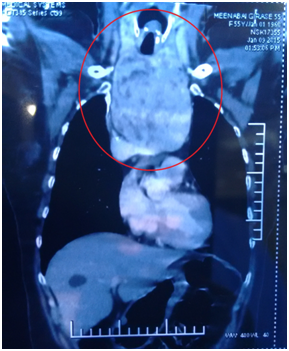

A 55year old reported to our cancer centre with a chief complaint of difficulty in breathing and eating from 2years. General examination was insignificant. Local examination revealed a diffuse swelling of left lobe of thyroid (Figure 1). Her medical history revealed hyperthyroidism from 2years. A provisional diagnosis of Thyroid swelling was made. Radiological examination was done. Computed tomography of neck revealed 12 x 8 x 7cm retrosternal mass arising from left lobe of thyroid with tracheal compression (Figure 2). There was no cervical lymphadenopathy.6‒10 Thyroid function test (T3, T4 and TSH) were done. T3 was 2.11nmol/l, T4 was 228.86nmol/l and TSH was less than 0.06uIU/Ml. Fine needle aspiration of the lesion gave a final diagnosis of nodular colloid goitre with cystic changes. Since T4 was high, patient was started on Tab Neomarkazole 2.5mg, Tab Inderal 80mg and Lugol Iodine solution orally for 5days to avoid Thyrotoxicosis. After 5days T3 was 0.98nmol/L, T4 was 180.36nmol/L and TSH was less than 0.05Uiu/Ml. Patient was taken for surgery.

Figure 2 Computed tomography of neck revealed 12 x 8 x 7 cm retrosternal mass arising from left lobe of thyroid with tracheal compression.